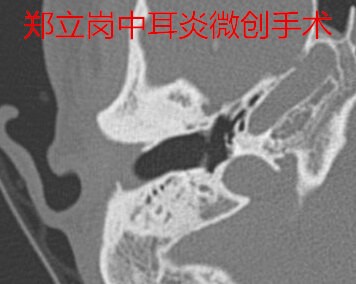

近半月余来双耳未再流脓,今门诊以"双侧慢性化脓性中耳炎"收住入院,拟进一步手术治疗。患者双侧鼓膜穿孔,左侧听力下降,右侧完全听不到。这次做的是右侧的中耳炎微创手术,准备右侧恢复后再做左侧的耳内镜微创手术。

插管全麻后就开始了手术,在耳内镜不用做任何的体表切口,直接翻起外耳道鼓膜皮瓣,翻起皮瓣后可以看到鼓室中无肉芽及胆脂瘤组织,听骨链是完整的,活动可。

取合适大小的耳屏软骨修剪后修补鼓膜,鼓膜修补好后检查了两遍确认没问题后就结束了手术。整个的手术用时约40分钟,非常的顺利。术后查房患者无明显的不适,无手术相关的并发症。